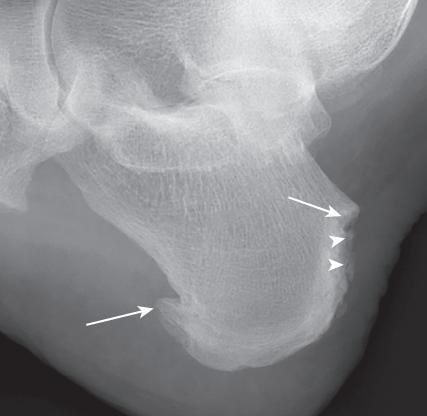

图8,毁损关节X光

图9,此为图8毁损关节的细节放大